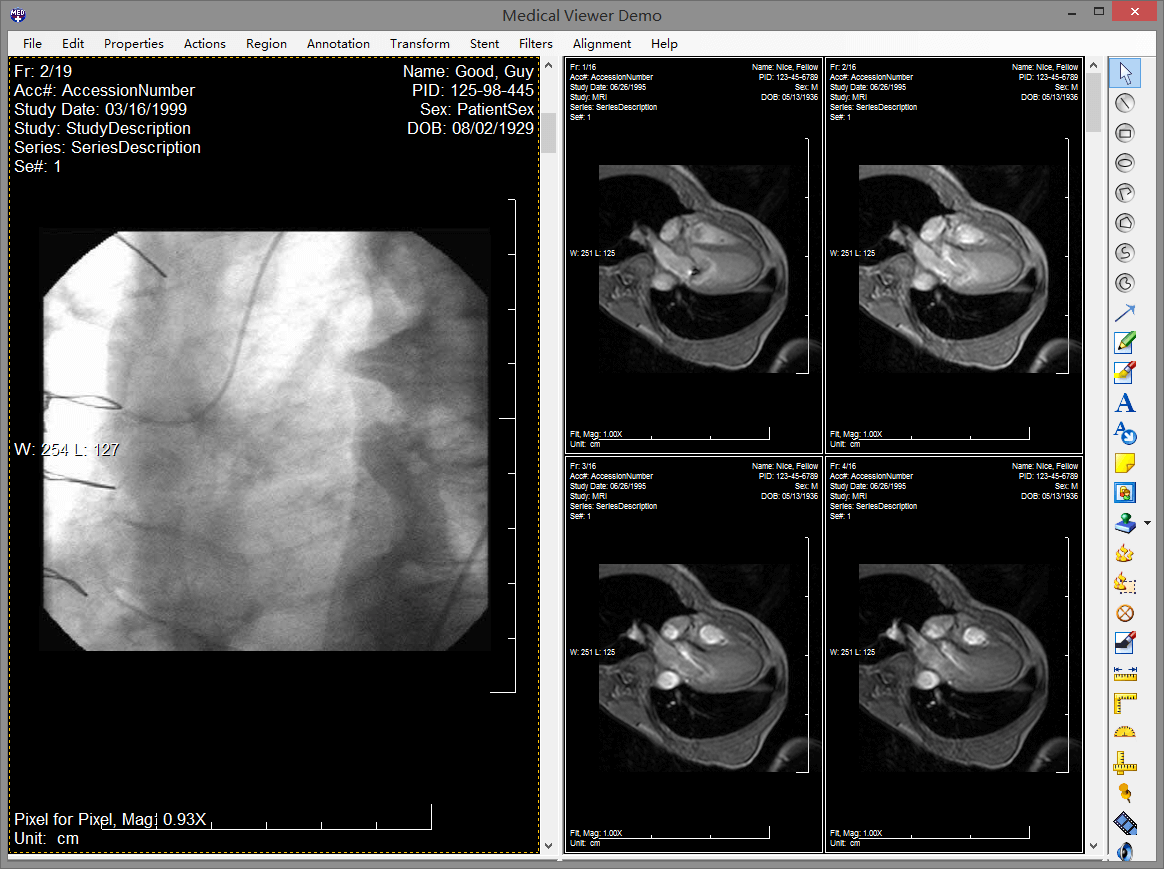

leadtools pacs能够使开发人员非常容易的开发一整套完整的pacs解决方案,组建企业级pacs服务器和客户端,实现dicom通信、查询、存储dicom影像数据。leadtools拥有成熟的pacs框架,您只需要修改logo就可以轻松构建一整套pacs系统。它包含了全套的权限、服务、存储、客户端、html5 web 端,而这一切都是基于多年大型医院需求的总结体现,并且已经完整的在超过150家医院真正部署。

leadtools 能够使您快速创建高质量、全功能和安全的基于web的医学影像工作站,您可以在上面查看3d图像、标注、测量、灰度等等。完全不需要部署任何的客户端,实现零空间占用。这样您就可以轻松的在iphone、ipad、android和windows phone上随时随地查看病人信息。一次开发,跨平台使用,您再也不必头疼需要为医院开发不同客户端了,只需要html5 web端就可以全平台浏览器支持。

windows、android、ios、winrt、html5、linux全面支持,让您可以在任何设备上查看医学影像。

leadtools为开发者提供了一套非常全面的示例代码库,它被包含在安装包中,开发者可以非常简单的部署、运行,学习leadtools的所有功能。其中包含整套pacs服务器和客户端源代码。

leadtools为开发人员提供了一个完整的框架,可用于创建强大的基于云计算的应用。利用网络服务器和工作机器,开发人员可以轻松创建任何种类的分布、网格或并行计算的应用程序。